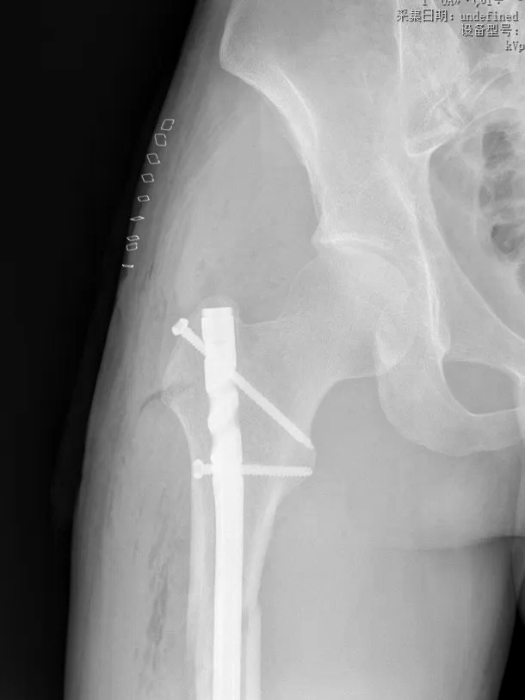

由李继松副主任医师、佘晗主治医师及刘兴医生组成的创伤团队的每一位成员都沉着应对、默契配合,在影像引导下精准定位骨折端,把控角度与深度,最终实现骨折端的完美复位。整个手术过程行云流水,既克服了该骨折复位难、固定要求高的技术痛点,又实现了微创化操作,术中出血量极少,患者生命体征平稳。历经1小时的精细雕琢,这台高难度手术以近乎完美的状态圆满结束。

术后,在骨科医护团队的细心指导与护理下,康复科同步介入,为患者制定个性化康复功能锻炼方案并全程指导,加速肢体功能恢复,术后第2天即可在床上进行简单肢体活动,疼痛症状明显缓解;术后1周,床上膝关节活动度达90°,髋关节活动度90°,肢体功能逐步恢复。复查影像学显示,骨折端复位精准、内固定位置稳固,完全达到临床理想标准,为后续愈合奠定了坚实基础。